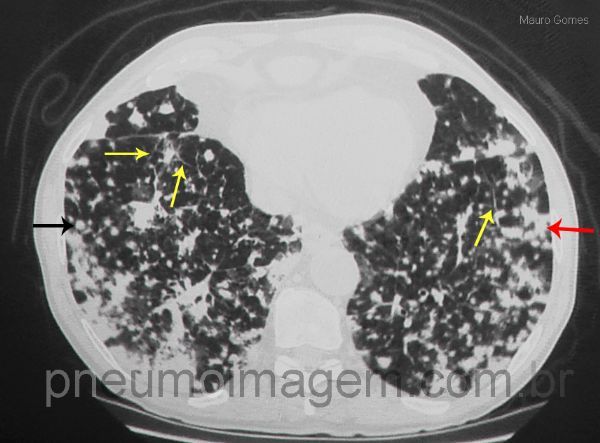

Nódulos difusos (seta preta), alguns deles confluentes (seta vermelha) e espessamento liso de septos interlobulares compatível com linfangite (seta amarela). Quando essas características são encontradas remotamente durante a evolução a partir de uma lesão pulmonar primária que provou ser um adenocarcinoma, e/ou em pacientes com história prévia de adenocarcinoma de pulmão tratado, a propagação aerógena intrapulmonar deve ser suspeitada. É importante ressaltar que as metástases aerógenas devem ser diferenciadas de múltiplas lesões síncrônicas no espectro do adenocarcinoma de pulmão.

Diffuse nodules (black arrow), some of them confluent (red arrow) and smooth interlobular septal thickening compatible with lymphangitis (yellow arrow). When these characteristics are found during the course remotely from a primary pulmonary lesion that proved to be an adenocarcinoma, and / or in patients with a history of treated lung adenocarcinoma, the intrapulmonary aerogenous spread should be suspected. Importantly, the aerogenous metastases should be differentiated from multiple synchronous lesions in lung adenocarcinoma spectrum.